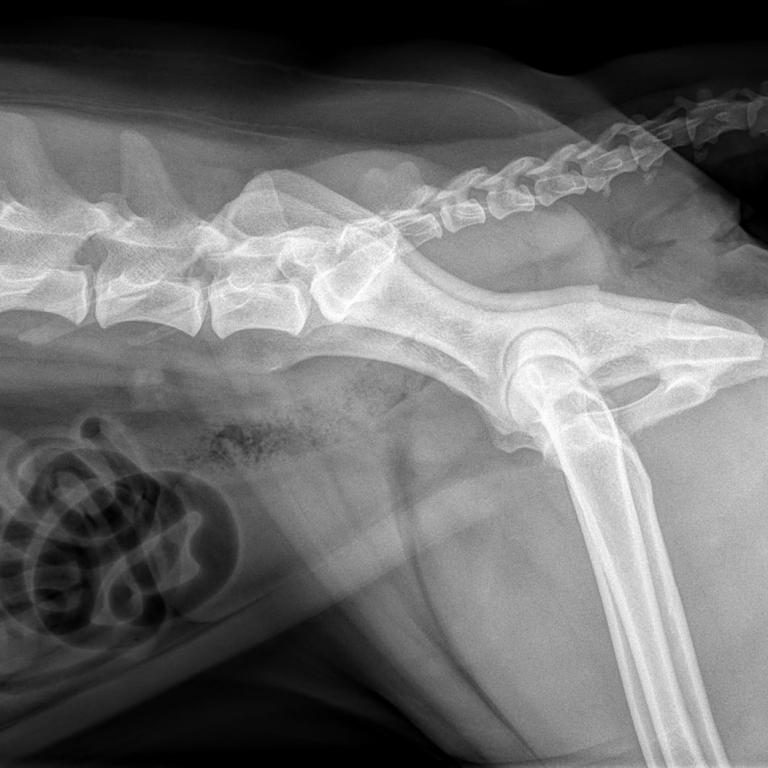

Unsere leistungsfähige Röntgenanlage ermöglicht die Anfertigung qualitativ hochwertiger Aufnahmen von der Katze bis zum Bernhardiner. Röntgenuntersuchungen sind vor allem bei orthopädischen Erkrankungen das Diagnostikum der Wahl, aber auch bei Herz- und Lungenerkrankungen, zur Darstellung von röntgendichten Fremdkörpern und zur Erkennung von Lungentumoren und -metastasen eignet sich die Röntgenuntersuchung hervorragend. Natürlich führen wir auch Zuchttauglichkeitsuntersuchung auf HD, ED und OCD durch.